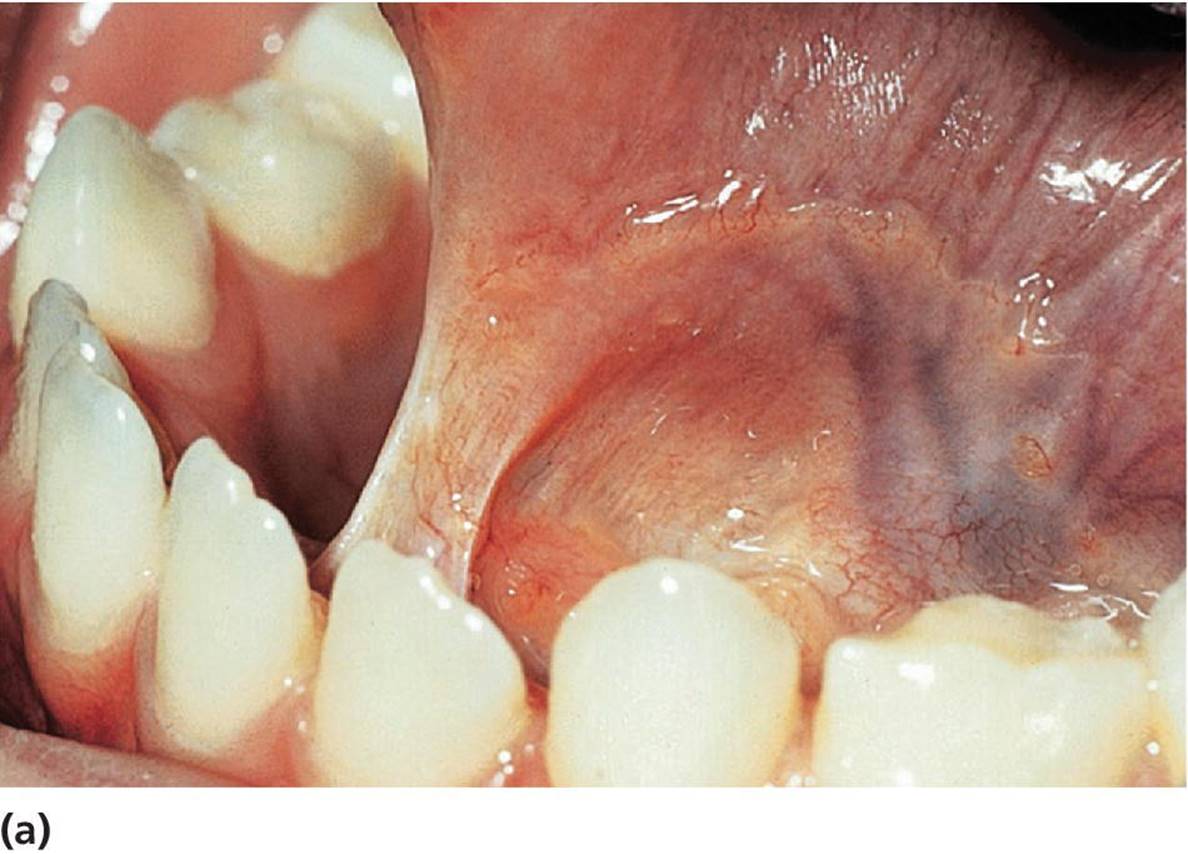

Ranula is essentially a large mucocele, located as a bluish swelling of the floor of the mouth (Figure 15.18). It arises from the salivary glands in that region. Due to extravasation or retention of mucus from excretory ducts of sublingual glands caused by trauma or infection, the extensive translucent swelling may occur.

Figure 15.18 Ranula located in the floor of the mouth.